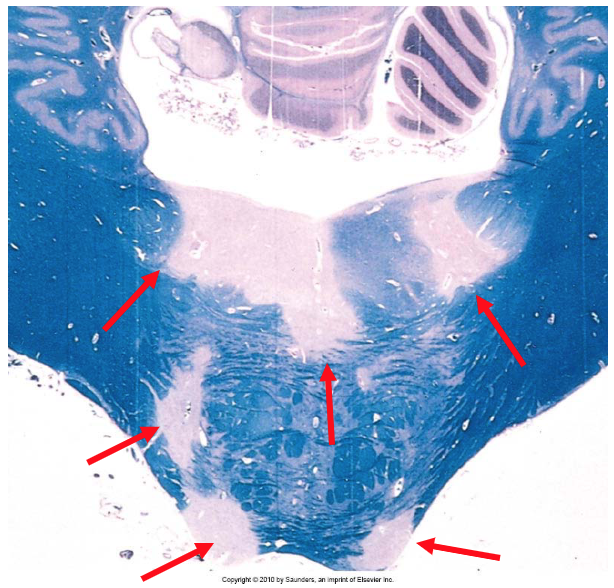

If the provided sample has been stained with Luxol-fast blue PAS, it is from what disease?

MS

unstained regions of demyelination

plaques (red arrows) seen around the 4th ventricle